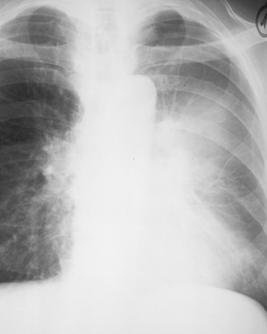

Fig. 15 – Abces pulmonar stang (imagine hidroaerica parahilar stanga cu nivel mare de lichid si pereti grosi imprecis delimitati)